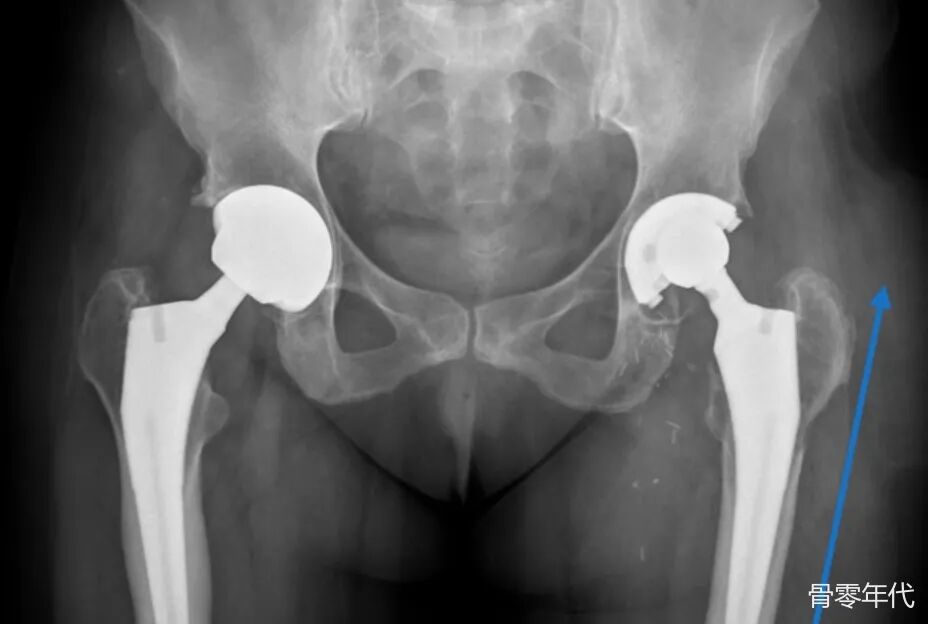

左腿髋臼部分有骨溶解区,股骨头因聚乙烯磨损而在杯内位置偏心,柄无松动迹象。箭头指示左侧大转子区域出现较为明显的放射性增加区域,暗示软组织肿块,后来手术确认为液体积聚。